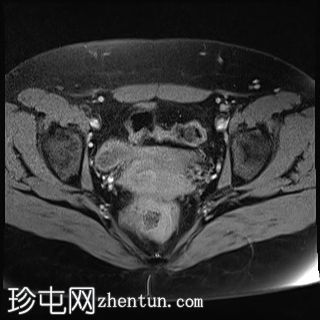

矢状位

T2加权像

双侧卵巢位置接近(卵巢相吻),左侧卵巢内可见一边界清晰的囊性病变,大小约3.1 × 2.7 × 2.9 cm,T1加权像呈高信号,T2加权像可见暗点征及内部暗点征。以上MRI特征符合卵巢子宫内膜异位囊肿的诊断。

右侧卵巢可见一囊肿,大小约为 2.8 × 2.0 × 2.2 cm,T1 加权像呈高信号,囊内可见液-液平面,提示囊内含有不同时期的出血性物质。由于对侧卵巢存在典型的子宫内膜异位囊肿,且该囊肿无强化,影像学表现强烈提示为另一子宫内膜异位囊肿。

子宫大小、轮廓及信号强度均正常,子宫内膜分区结构完整。未见局灶性肌层病变,子宫内膜厚度在正常范围内。

左侧盆腔可见少量游离液体。